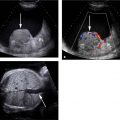

Annirudh Kohli The acute abdomen is a common presentation to the emergency services of a medical facility. The imaging specialist is now well armed with a full complement of diagnostic and interventional modalities to evaluate the acute abdomen as well as utilize them as a guide for therapeutic procedures. A plain X-ray of the abdomen is usually the first investigation ordered, both erect and supine. These are very useful to detect bowel perforation, seen as free air in the abdominal cavity especially under the domes of diaphragm on the erect X-ray. Supine and erect films are also useful to detect bowel obstruction by demonstrating fluid levels on the erect film and dilated loops on the supine film. Additionally, presence of calculi, foreign bodies, location and placement of tubes in the abdomen are demonstrated on plain X-rays. A chest X-ray is also mandatory as this is the most sensitive means to demonstrate free air under the domes of the diaphragm. A number of chest pathologies may present clinically as an acute abdomen, such as pneumonia, CCF, dissecting aneurysm, pulmonary infarction, pleural effusions and pericarditis. Secondary effects of an acute abdomen such as pleural effusions, atelectasis, aspiration pneumonia, acute lung injury may be also visualized on the chest X-ray. Finally, a chest X-ray on admission forms as a good baseline study for postoperative complications such subphrenic abscess which may be evident only after comparing with the previous X-rays. Sonography is an indispensable tool in the evaluation of the acute abdomen as it is portable and can be done at the bedside. It is quick and the modality of choice for evaluating the gallbladder, genitourinary system, detecting free fluid and compares as well as CT in evaluation of the liver. It is also very useful for evaluating the lower chest for presence of effusions which may not have been visible on a chest X-ray or to clarify an opacity on the chest X-ray whether parenchymal or pleural. Unfortunately, sonography has its share of limitations, it is operator dependent, bowel gas, obesity, wound dressings may interfere with sonographic evaluation. CT scan is the modality of choice as it is not limited by factors which interfere with sonographic evaluation. The only disadvantage is the need to transport the patient to the CT scan suite. However, the information gained outweighs the risk of transportation of the patient. CT studies may be done with or without contrast.